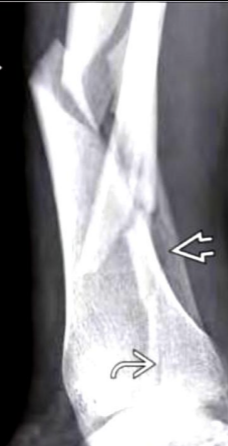

A

Fx en espiral

Q

Fx tibia trasversa